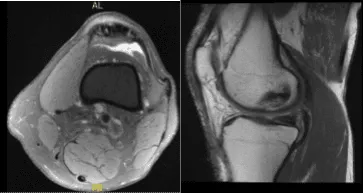

Al paciente le pusieron una inyección de cortisona, que le ayudó de forma transitoria, pero el dolor volvió. Hay una leve degeneración mucoide del ligamento cruzado anterior. Existe un esguince leve del ligamento colateral medial proximal con edema periligamentoso de tejidos blandos asociado que se extiende a lo largo de la cápsula posteromedial.

Hay una leve tendinosis de inserción poplíta. Hablamos sobre las opciones de tratamiento y el paciente optó por el manejo quirúrgico, incluyendo los riesgos y complicaciones de la cirugía y la necesidad de inyección de cortisona y fisioterapia.